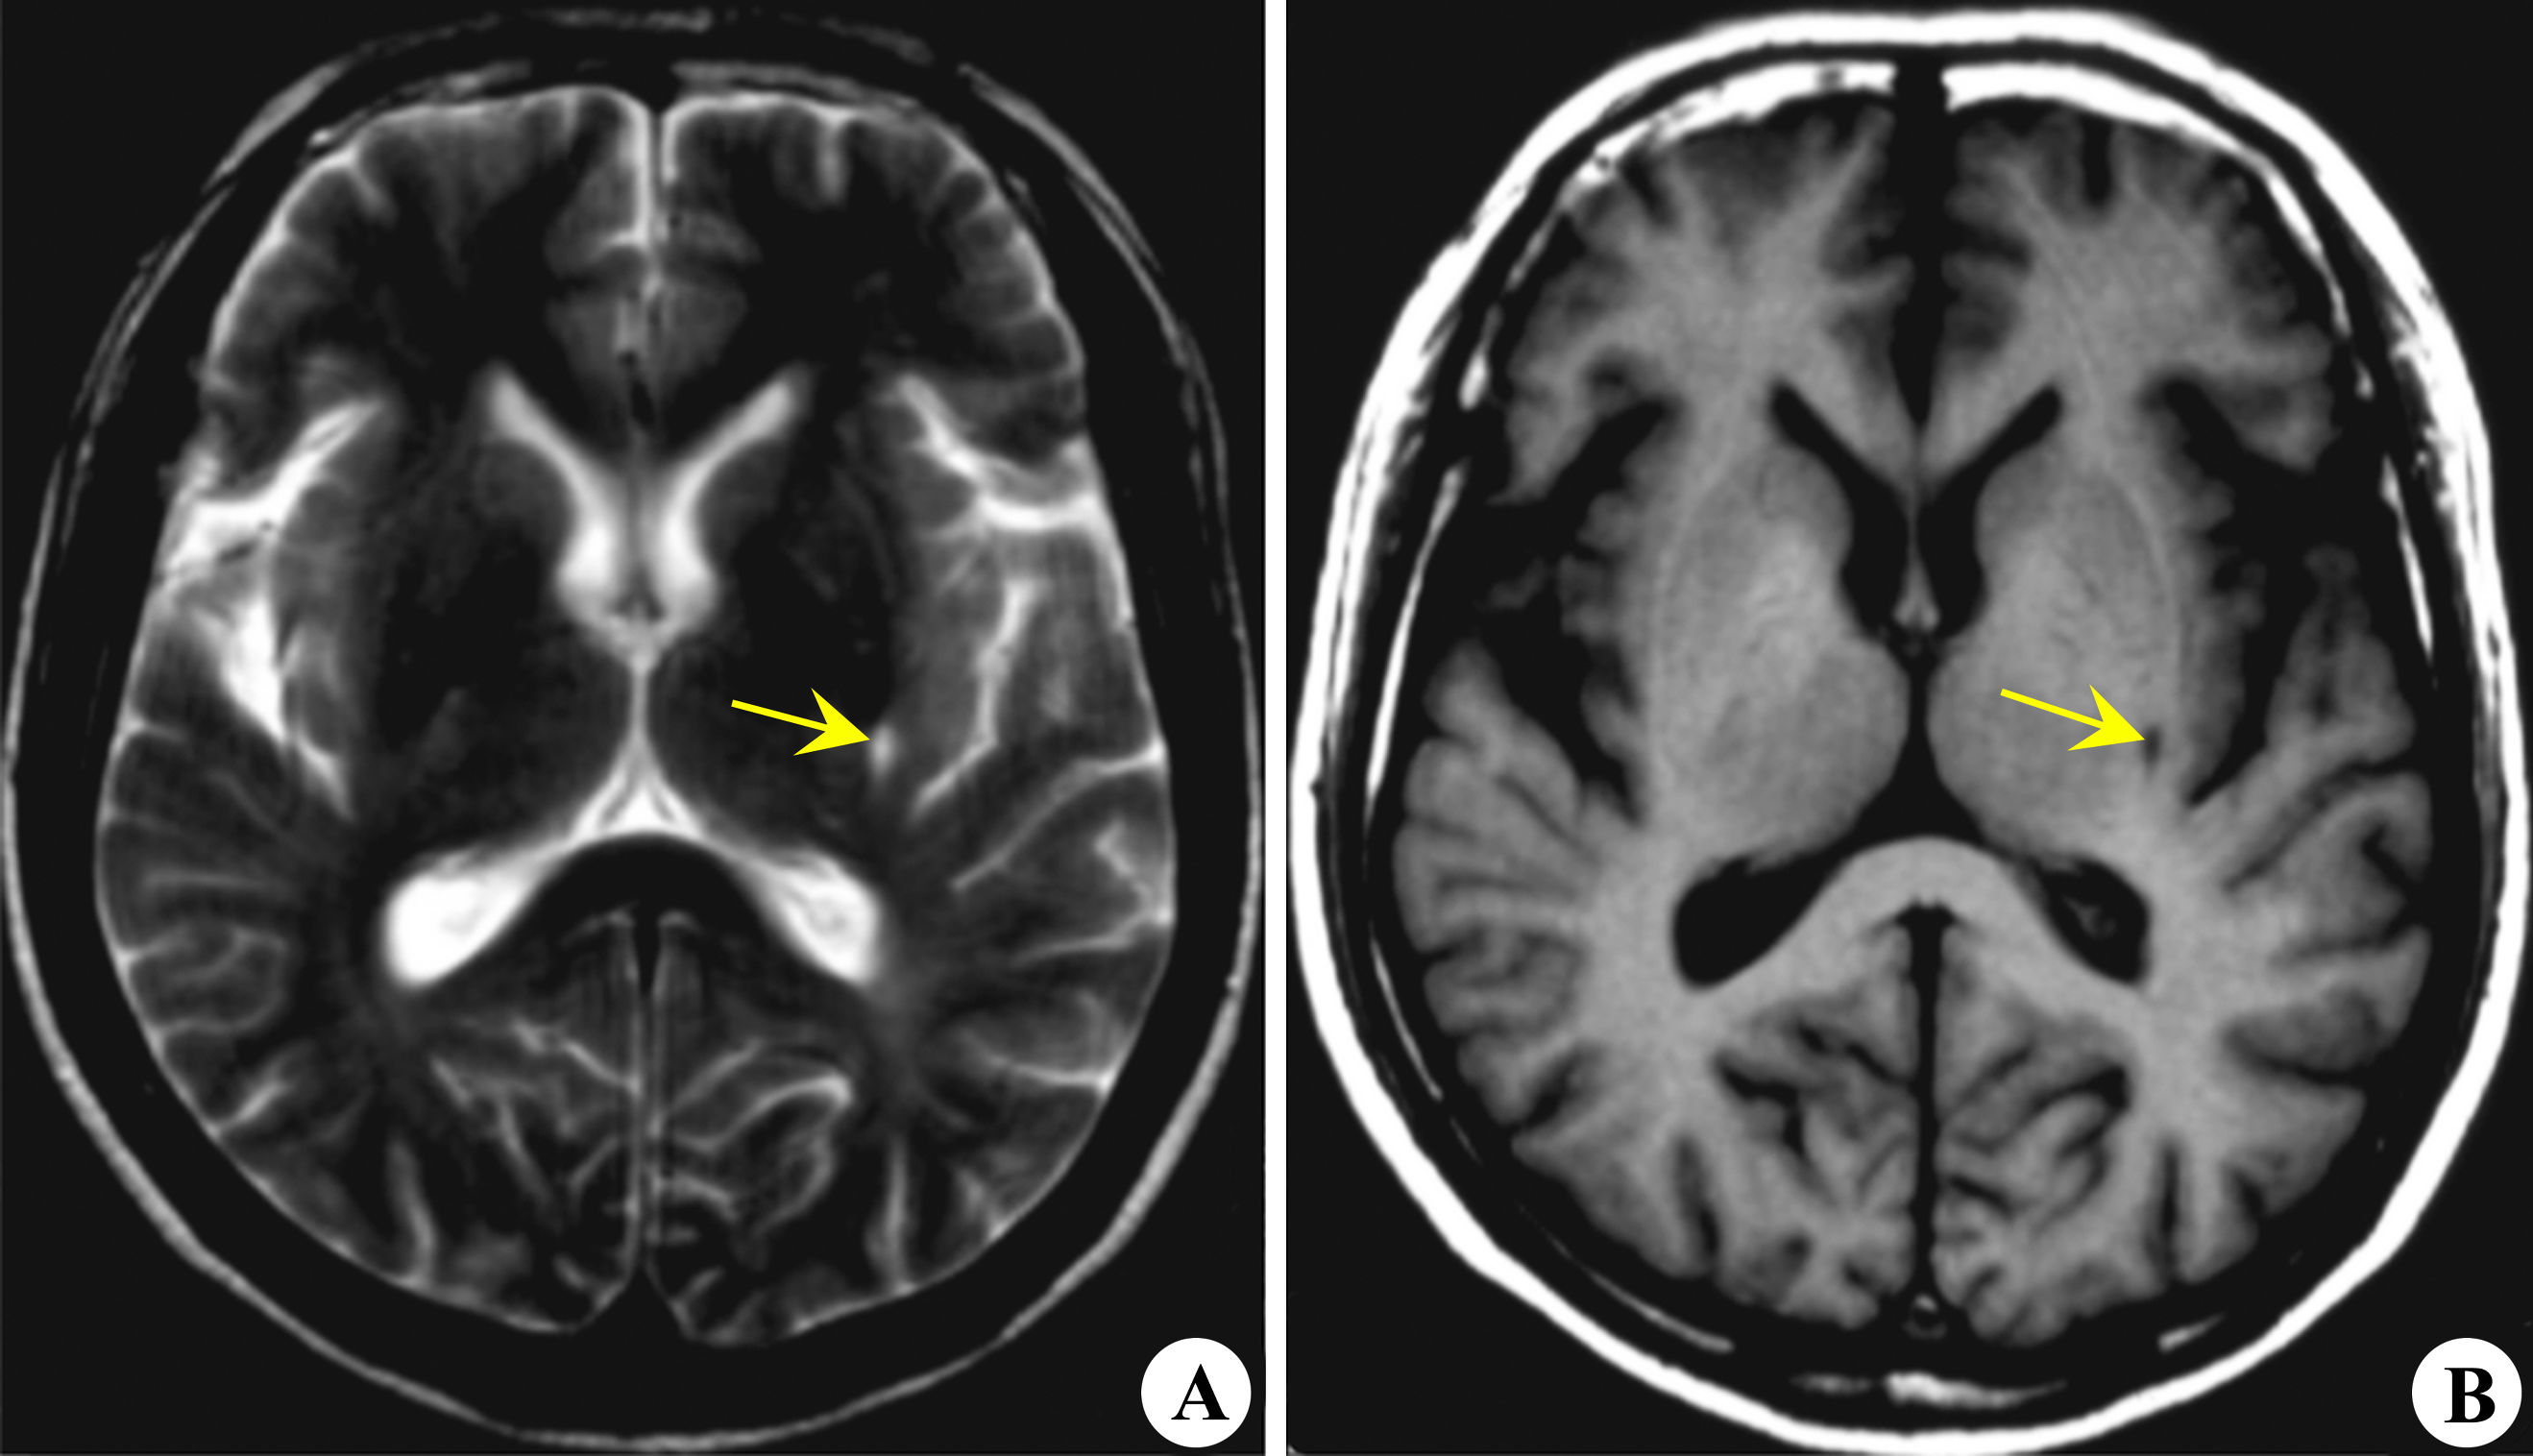

左侧基底节区腔隙性脑梗死

腔隙性脑梗死,简称“腔梗”,它特指放生在基底节、丘脑、脑室旁、脑干等区域的小的梗死灶,直径一般在0.1~0.2毫米,病理基础是微小动脉硬化、闭塞造成的脑组织缺血性微梗死,缺血、梗死后的脑组织液化后被体内的吞噬细胞清除,形成小的腔隙。这些腔隙小的直径仅为0.2毫米,大的可达15~20毫米,大多数为2~4毫米。